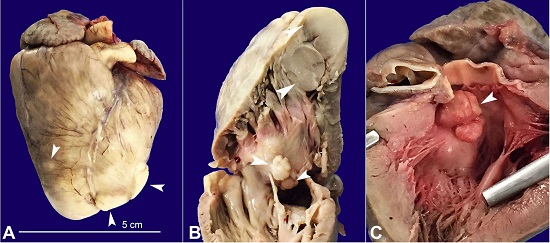

The skin examination was normal. The heart weighed 25 g (average heart weight adapted for age and birth weight: 19.1 ± 2.8g) and showed nine cardiac nodules diffusely distributed within the atrial and ventricular chambers, measuring from 0.2 to 1.5 cm. They were firm and white, the biggest one had 1.5 cm, was located in the interventricular septum, protruded into the left ventricular outflow tract, and almost entirely obstructed the aortic valve (Figures 1A, 1B, 1C).